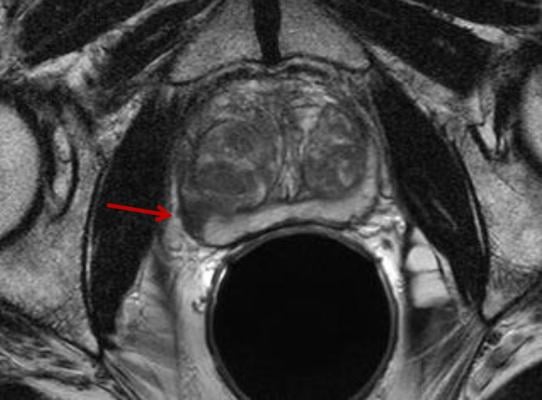

And some men with prostate cancer have more of the protein than others. For prostate cancer that has spread to a small number of areas in other parts of the body. An mri (magnetic resonance imaging) scan uses magnets to create a detailed picture of your prostate and the surrounding tissues. The prostate gland is composed of different types of tissue, divided into zones: According to the paper by patel, et al., It is used to treat early stages of cancer and helps to relieve you from symptoms such as pain. Molecular imaging, a field where a radiotracer is used as the imaging agent, is a useful tool for both detecting and treating prostate cancer. T4 prostate cancer may involve the pelvic floor muscles, the urethral sphincter, the bladder itself, the rectum, or the levator muscles or the pelvic wall. Chade dc, eastham j, graefen m, hu jc, karnes rj, klotz l, et al. Recently, it is suggested that multiparametric mr imaging of the prostate could improve the diagnostic accuracy of the prostate cancer. To help make sense of the options, we spoke with michael zelefsky, vice chair of. Brain metastases from prostate cancer are uncommon and their imaging appearance has not been well defined. Radiation can occur at different times in your treatment plan: